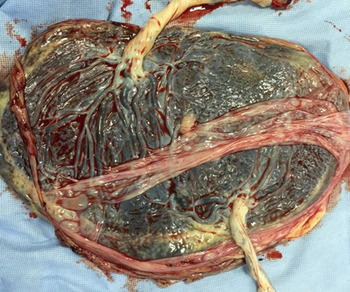

A 30-year-old primipara who conceived spontaneously was diagnosed with a monochorionic (MC) diamniotic twin pregnancy through ultrasonographic findings at 9 weeks’ gestation because there were two fetuses. They were in a common gestational sac, and each had its own amniotic cavity. The primipara was referred to us at 12 weeks’ gestation for the management of her twin pregnancy. At 26 weeks, serial scans showed that the fetuses had a different sex. No abnormalities were found in their anatomy, including the genital organs. The twins were delivered via cesarean section at 38 weeks’ gestation. Apgar scores and pH values were normal. Twin A was a phenotypically normal female, with a birth weight of 2612 g, and Twin B was a phenotypically normal male, weighing 2458 g. Histological examination of the placenta confirmed MC diamniotic twinning (see Figures 1 and 2). Karyotyping was performed on each umbilical cord blood and revealed the chimeric karyotypes 46,XX[15]/46,XY[15] and 46,XY[21]/46,XX[9] for Twin A and Twin B, respectively. Ultrasonography determined normal female and male internal genitalia concordant with their phenotypes (see Figures 3 and 4). Karyotyping was performed again from blood samples at 7 months of age. The results confirmed that the twins had similar chimericg karyotypes: 46,XY[7]/46,XX[13] in Twin A and 46,XX[9]/46,XY[11] in Twin B.

Fig. 1. Macroscopic imaging of the placenta revealed that the twins were monochorionic–diamniotic.